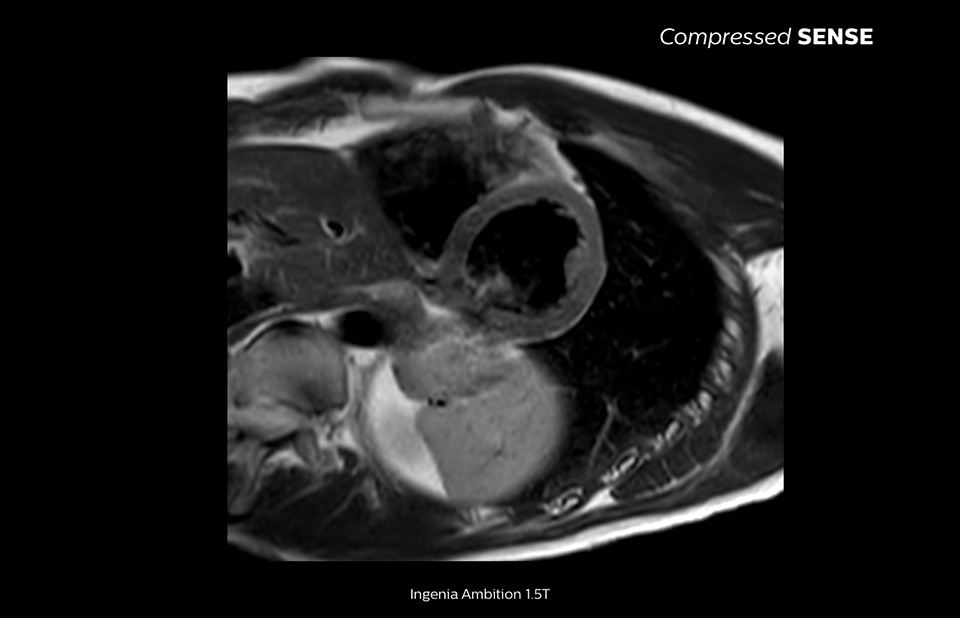

Compressed SENSE can accelerate most MRI scan sequences without sacrificing image quality, which allowed KOYASU Neurosurgical Clinic (KNC) to shorten its MRI time slots. As a result, KNC increased the throughput of their MRI scanner with an average of three additional patients per day.

Learn more about the main principles of Compressed SENSE MRI software and how it introduces a paradigm shift in productivity. Compressed SENSE was designed around image quality, and it can accelerate scans, increase spatial resolution and enhance the patient experience for clinical MR imaging.

The MRI staff at Kurashiki Central Hospital incorporated Compressed SENSE into most of the brain, spine, abdominal, and cardiac examination protocols on their Ingenia 1.5T, resulting in fast and high-quality MRI scans, which is welcomed by patients and staff.